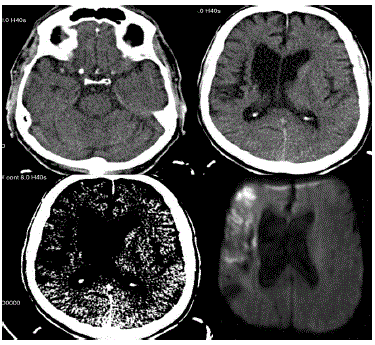

Paciente LSM, masculino, com 62 anos é admitido na emergência com um quadro semelhante ao de um insulto vascular e com início há três horas. A acompanhante trouxe exame anterior que demonstrava sequela de insulto vascular isquêmico na ínsula com extensão a coroa radiada à direita.

As imagens realizadas no momento da admissão estão a sua disposição.

Baseado nas imagens disponibilizadas, qual o seu diagnóstico?